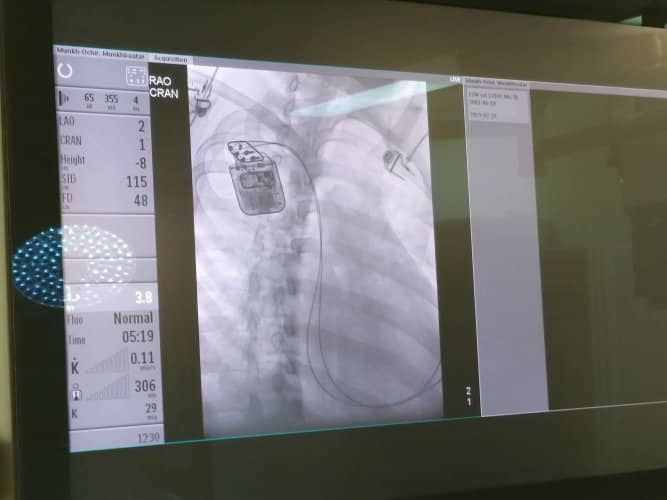

Улсын гуравдугаар эмнэлгийн Зүрхний хэм судлал, Зүрхний дутагдлын баг, Эрчимт эмчилгээний нэгдсэн тасаг, Ангиографийн оношилгоо эмчилгээний хамтарсан баг Зүрхний хүнд дутагдалтай 18 настай залууд зүрхний агшилтыг дэмжигч төхөөрөмж суулгах мэс заслыг амжилттай хийлээ. Энэхүү эмчилгээ нь хүнд болон дунд шатны зүрхний дутагдал өвчнөөр эмчлүүлж буй нийт эмчлүүлэгч нарт хэрэглэгдэх боломжтой ба биед суулгасан цахилгаан төхөөрөмжийн тусламжтайгаар зүрхний агшилтын үед цахилгаан сэрэлийн цочролийг үзүүлсэнээр зүрхний дараа дараагийн агшилтыг дэмжиж өгдөг юм.